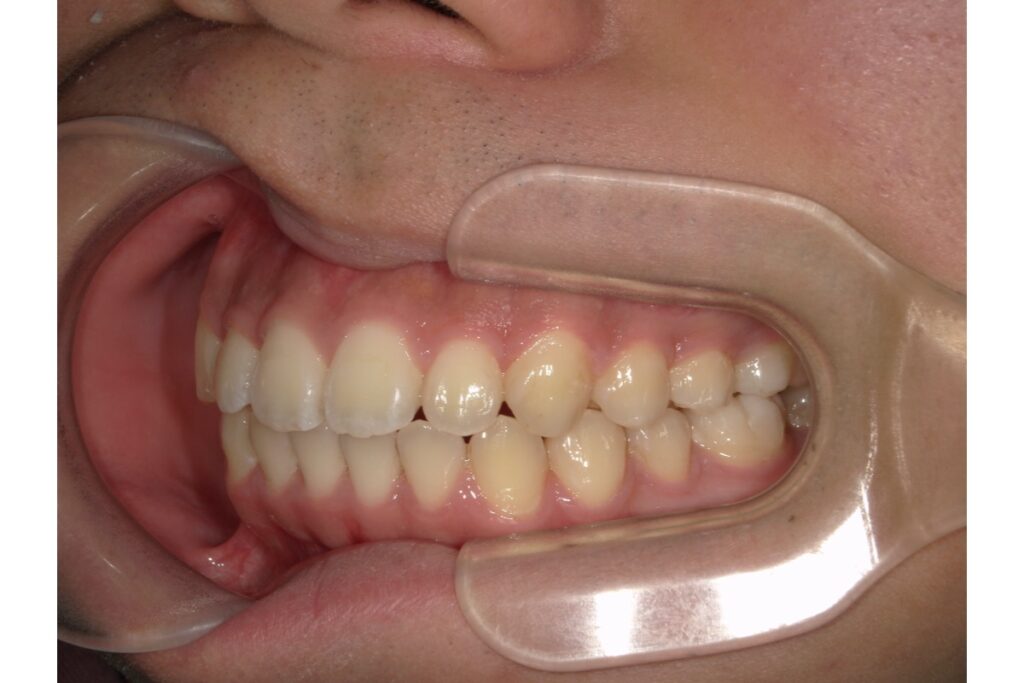

治療が終わり、アタッチメントを外した後の歯並びは、とても自然で美しい仕上がりになります。

インビザラインはワイヤー矯正と違い、治療中に装置をつけた「跡」が残りにくく、透明感のある歯の質感がそのまま残るのが大きなメリット。

- 歯並びが整い、笑顔が自然に見える

- 歯の表面に違和感がない

- 着色やざらつきもなく、ツルっとした手触り